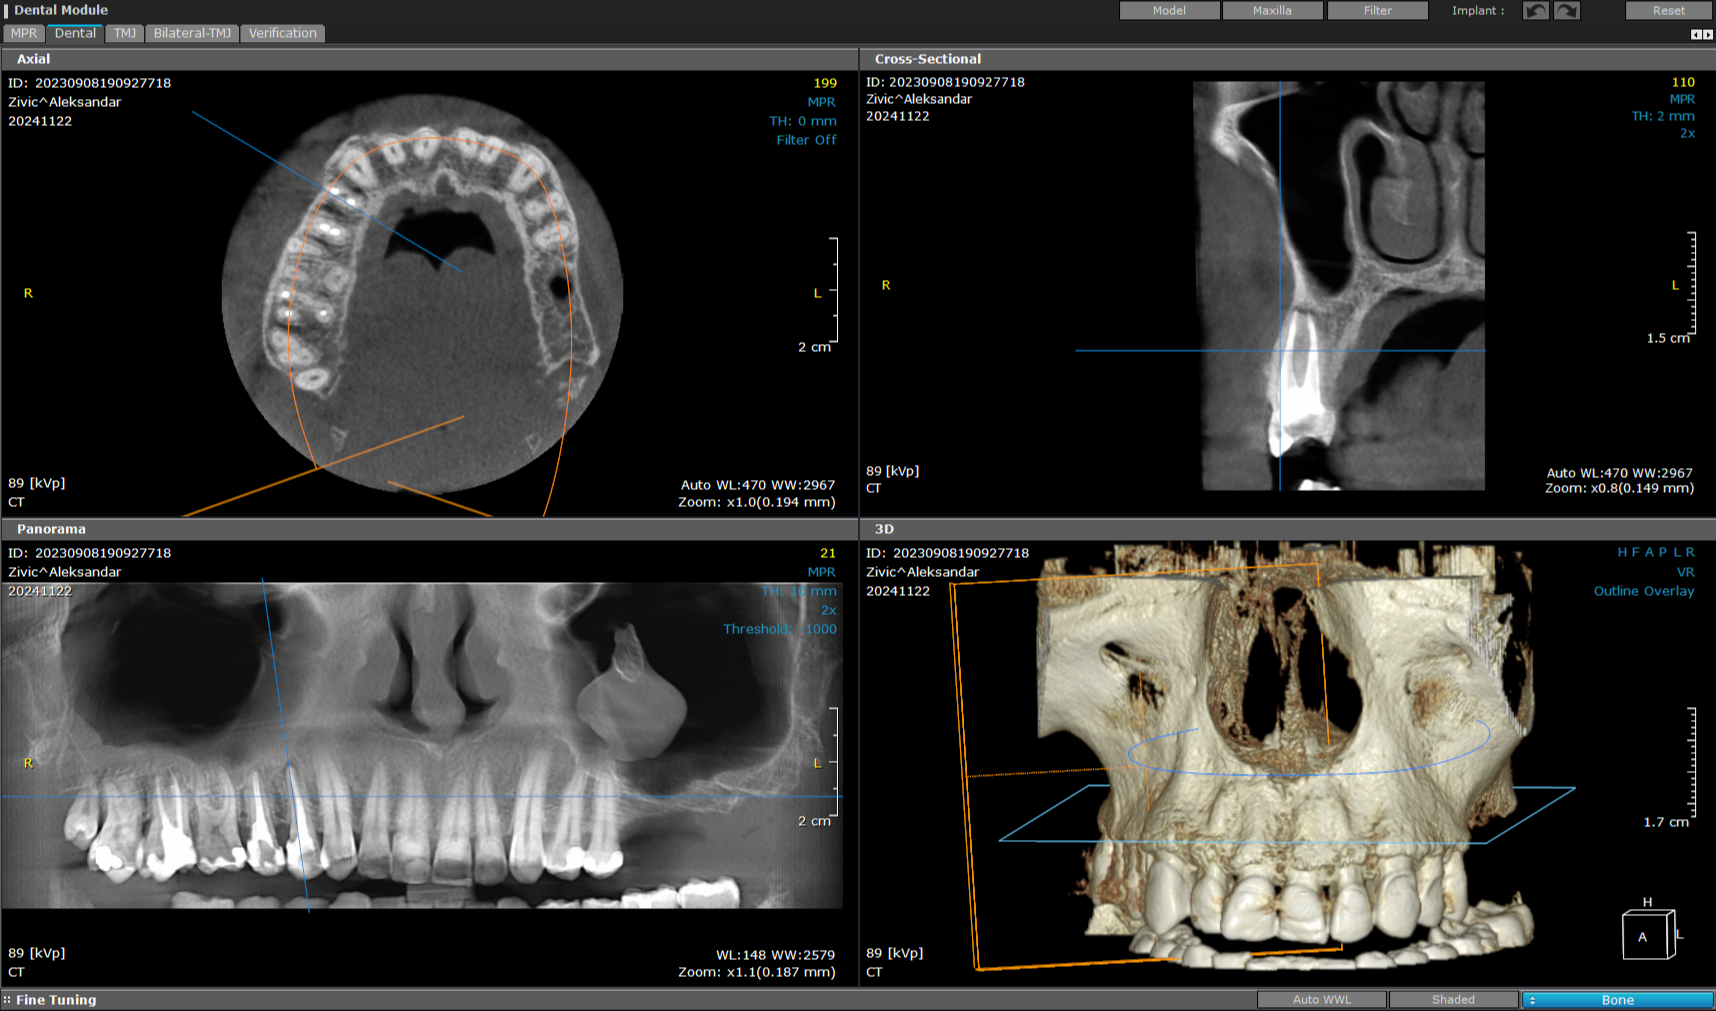

3D snimanje zuba predstavlja savremenu dijagnostičku metodu u stomatologiji koja omogućava trodimenzionalni prikaz zuba, vilice i okolnih anatomskih struktura. Ova tehnologija, poznata kao CBCT (Cone Beam Computed Tomography), pruža izuzetno precizne informacije koje stomatolozima pomažu u planiranju terapije i izvođenju složenih stomatoloških procedura.

Za razliku od klasičnih 2D snimaka, 3D snimci omogućavaju detaljan prikaz kosti, položaja zuba, nervnih kanala i sinusa, što je posebno važno kod planiranja ugradnje implantata, ortodontske terapije, endodontskog lečenja i hirurških intervencija.

CISTE I PATOLOŠKE PROMENE

3D dijagnostika omogućava rano otkrivanje promena koje se ne vide na standardnim snimcima.

Jedna od najvećih prednosti 3D snimanja zuba je izuzetna preciznost i mogućnost analize svakog detalja. Za razliku od tradicionalnih 2D snimaka, gde se strukture preklapaju, 3D tehnologija omogućava slojevito prikazivanje zuba, kostiju i okolnih anatomskih struktura.

To znači da stomatolog može jasno da vidi položaj živaca, debljinu kosti i potencijalne komplikacije pre same intervencije. Na taj način se smanjuje rizik i povećava sigurnost svakog zahvata, posebno kada je u pitanju ugradnja implantata ili složeniji hirurški zahvati.